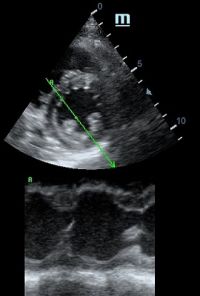

Но как же провести стандартные измерения в М-режиме, если мы его не использовали? На помощь приходит функция Free Xros M – анатомический М-режим. Имея записанную в память прибора видео петлю, мы можем провести линию М-режима в любом месте, при этом корректируя изначально не оптимальный угол.

Возможности применения функции многогранны: от измерения толщины стенок левого желудочка, движения створок митрального клапана и кооптации нижней полой вены до оценки сократимости миокарда как глобально, так и по сегментам.